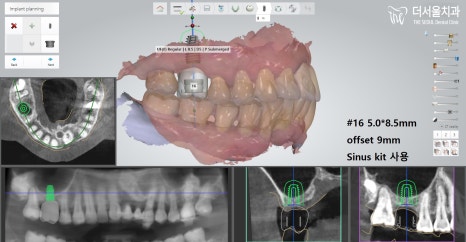

그렇기에 판교 치과 에서는

해당 방법을 시행하는데 있어

컴퓨터 분석 방법을 이용했습니다.

컴퓨터 분석을 이용하여 확인한 결과,

뼈이식을 어떻게 하면 좋은지

계획을 꼼꼼히 수립 후,

그에 걸맞게 시행했습니다.

우선 이미 빠져있는 # 26에

뼈를 옮겨 심었으며,

픽스처와 지대주, 크라운 세팅으로

먼저 수술을 끝마쳤습니다.

다음은 # 16 뼈이식 및 픽스처 식립으로

많은 골소실이 있었던 곳이라

골유착에 있어 더 오랜 기간 걸릴 수밖에 없었습니다.